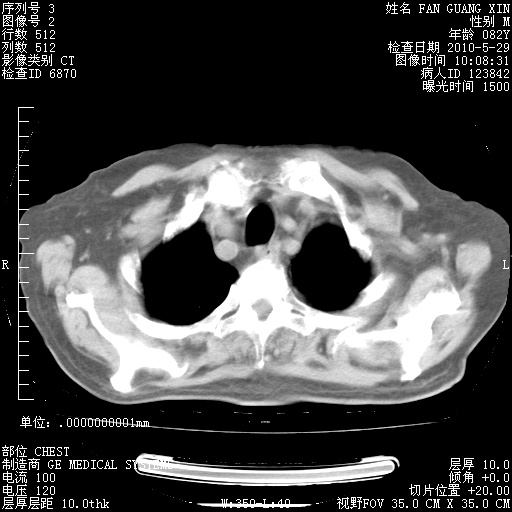

再治疗10天后的肺部CT

再治疗10天后的肺部CT 纵膈窗

阅读此次胸部CT,肺间质渗出性改变较入院时有吸收。目前从体温、白细胞、中性分叶明显增高,肯定存在细菌感染(发生医院感染哦,若无消化道及泌尿系统等感染的依据,肺部感染可能大)。若你院头孢哌酮舒巴坦钠耐药率较高,同意你的方案,若48小时体温仍高,可考虑使用碳青霉稀类抗菌药物,同时可予超声雾化、注意滴数时加大液体量。白蛋白33.30g/L较低哦,需加强营养等支持治疗。